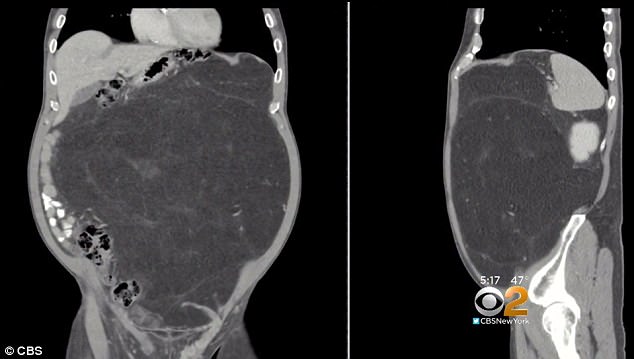

У жителя американского города Хобокен, штат Нью-Джерси, удалили злокачественное новообразование весом 14 килограммов, которое он принимал за пивной живот. Об этом сообщает издание Daily Mail.

63-летний Кевин Дэли заподозрил неладное после операции на сердце в 2015 году. Он сбросил 15 килограммов, однако размер живота остался прежним. В декабре 2017 года мужчина убедил врача сделать ему компьютерную томографию, несмотря на протесты страховой компании, считавшей это ненужной тратой.

Томография показала, что большую часть брюшной полости Дэли занимает огромная липосаркома. Новообразование росло в его животе около 10 лет. Как правило, опухоль замечают быстрее, поэтому липосаркома таких размеров - редкость.

Операция, во время которой у Дэли удалили опухоль и поглощенную ей почку, продолжалась шесть часов. Поскольку обычно липосаркомы распространяются медленно и не сопровождаются метастазами, врачи дают хороший прогноз.